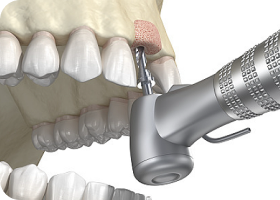

03

디지털 수술 가이드

잇몸을 절개하는 기존의 방식과 달리,

임플란트 식립 위치에 2mm 정도의 작은 구멍을 뚫어 식립을 진행하여

잇몸 손상과 통증은 줄이고, 빠른 회복이 가능합니다.